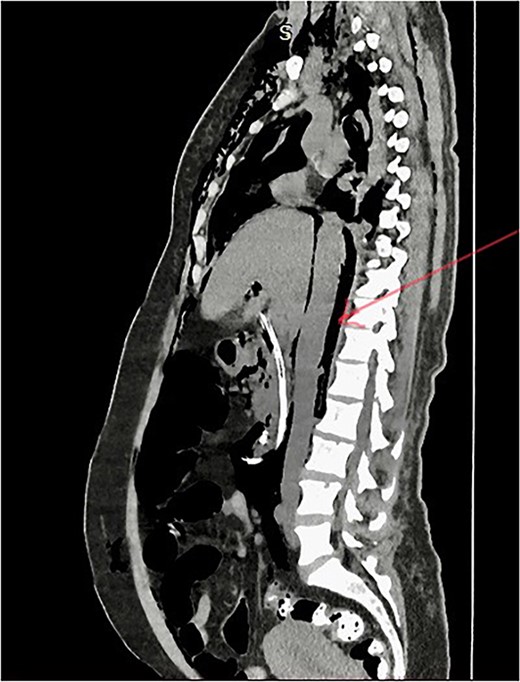

Post-ERCP NCCT abdomen shows pneumo-retroperitoneum (red arrow).

She has undergone a semi-elective ERCP in a semi-prone position, under sedation with propofol target-controlled infusion. Major papillae identified with side viewing endoscopy. Guidewire was inserted into CBD, and a cholangiogram was done. It showed dilated CBD up to 1.3 cm, mild dilated hepatic ducts, and a large radiolucent area in the distal CBD (around 1.5 cm). Sphincterotomy was done with a sphincterotome, and the ampulla was dilated up to 1.5 cm with a balloon dilator. Then, a balloon retrieval was attempted and failed, probably due to a stone sticking to the CBD wall. Then, a mechanical lithotripter was used to break the stone, but it failed, damaging the instrument. During the procedure, her oxygen saturation dropped to 75–80%, and she developed surgical emphysema in the face, neck, and upper chest region. In addition, she developed abdominal distention as well. Immediately, she underwent CBD stenting with a 12-cm, 10 French Gauge double pigtail biliary stent and changed her position to supine. Then, she was intubated with rapid sequence induction, and a nasogastric tube was inserted and transferred to the surgical intensive care unit. Post-ERCP, non-contrast computed tomography (NCCT) of the abdomen and chest showed extensive pneumo-peritoneum and retroperitoneal gas with subcutaneous emphysema (Figs 2 and 3). There was no evidence of air leakage on NCCT and no clinical features of peritonitis on subsequent days. So she was managed non-surgically with nasogastric tube (NG), nil by mouth, intravenous fluids with intravenous antibiotics. Clear fluid was started after 24 hours slowly via NG.

Management of ERCP-related complications depends on the type of perforation and the patient’s clinical condition. Type 1 perforations are managed with surgical repair [15]. Type 2 perforations are mainly managed conservatively, but some cases with clinical findings of peritoneal signs and sepsis and those with retroperitoneal or peritoneal fluid on CT require surgical repair [15]. Type 3 perforations are usually managed conservatively. Type 4 perforations are also generally managed conservatively, as these are no actual perforations [6, 14] In this case, the patient developed surgical emphysema and abdominal distention suggestive of perforation. She developed respiratory compromise due to pneumo-peritoneum, and her oxygen saturation was dropped during the time of procedure. Therefore, the clinical diagnosis of perforation was made, and the patient was intubated and managed conservatively in the ICU during the post-ERCP period without any need for surgical perforation repair. Post-ERCP, NCCT showed extensive pneumo-peritoneum and retroperitoneal gas with surgical emphysema.